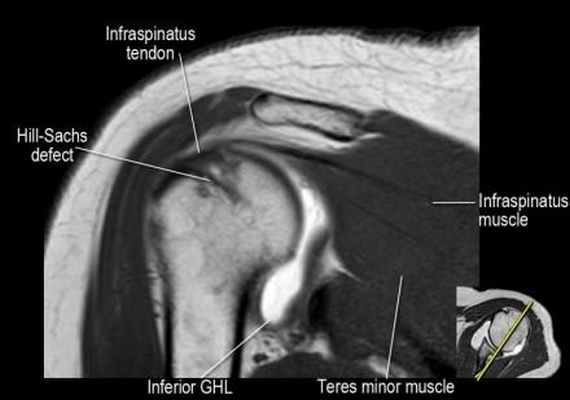

- обратите внимание на верхние отделы суставной губы и прикрепление верхней плече-лопаточной связки. На данном уровне ищется SLAP-повреждение (Superior Labrum Anterior to Posterior) и варианты строения в виде отверстия под сутавной губой (sublabral foramen - подгубное отверстие). На этом же уровне по задне-боковой поверхности головки плечевой кости визуализируются повреждение Хилл-Сакса.

- волокна сухожилия подлопаточной мышцы, создавая бицепитальную борозду, удерживают сухожилие длинной головки двуглавой мышцы. Изучите хрящи.

- обратите внимание на небольшое повреждение Хилл-Сакса